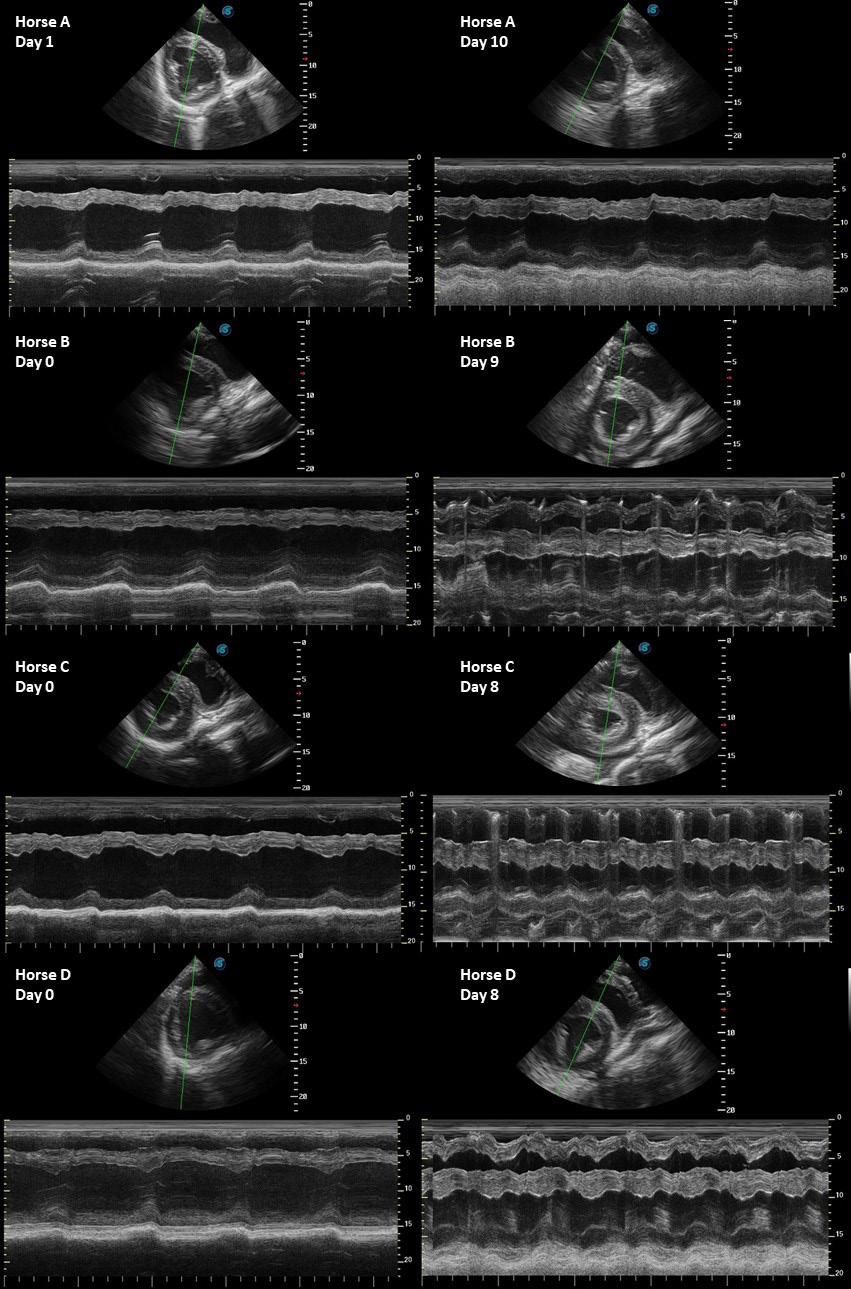

Echocardiographic evaluation of horses challenged with African horse sickness virus

African horse sickness (AHS) is an infectious, often fatal viral disease of equids with a severe impact on the equine industry in subSaharan Africa. Clinicopathological mechanisms are poorly understood, and there is limited information on the degree and type of cardiac involvement, especially during the course of the disease.

This study followed four horses experimentally infected with African horse sickness virus (AHSV) as part of a vaccine trial, to describe echocardiographic changes during the course of the disease. Echocardiography was performed once prior to infection, and daily from infection to humane euthanasia of each subject. Basic objective and subjective (eFoCUS) evaluations of all appropriate echocardiographic variables were performed.

An increase in diastolic myocardial thickness and a decrease in the size of the left cardiac chambers during diastole and systole were consistent findings on the last day of evaluation of each subject and suggestive of hypovolaemia. The cause of the suspected hypovolaemia was not investigated, but increased vascular permeability causing third space volume loss was considered the most likely cause, as this is associated with the disease process. During the eFoCUS evaluation substantial and perfect interobserver agreements were found for an

increase in myocardial thickness and diminution of the left ventricle, respectively, suggesting that these variables could be used to subjectively evaluate cardiovascular status in clinical cases in an emergency setting. In addition, perfect interobserver agreement for impaired diastolic function, and almost perfect agreement for

pericardial effusion, was found during the eFoCUS evaluation of the final data sets for each subject. Further studies are needed to confirm the presence, quantify the severity, identify the cause and significance of these findings in both clinical and experimental environments.